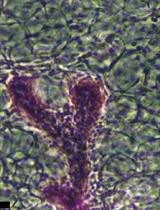

Graphical overview of integrated workflow for three-dimensional visualization of human skeletal muscle stem cells. After the percutaneous muscle biopsy, cut ~25–100 mg of the sample and arrange it according to the desired orientation → Mount sample for sectioning, embed in mounting medium, and freeze in liquid nitrogen-cooled isopentane → Using a cryostat, generate tissue cross-sections in an alternating collection method of 20 μm intervals and place on subbed glass slides → Fix and block sections before incubating in a cocktail of primary antibodies specific for satellite cell nuclei (anti-Pax7) and muscle membrane (anti-laminin) overnight. The following day, incubate sections in the appropriate secondary antibodies (Pax7: goat anti-mouse IgG1 biotin conjugated; laminin: goat anti-rabbit Alexa Fluor 488), apply signal amplification using streptavidin-horseradish peroxidase and tyramide 594 conjugate before counterstaining with DAPI, add mounting media, and coverslip → Using a confocal microscope, search for Pax7 signal, confirm overlap with DAPI adjacent to laminin labeling, apply appropriate laser channels, determine z-stack size, and acquire images in high-pixel-resolution format → For image post-processing, in the software’s three-dimensional viewer, modify individual channel histograms to optimize image quality and save as a TIFF.

Intense physical activity can induce acute skeletal muscle damage that can persist for multiple days and even up to a few weeks [2]. In individuals with muscle-specific diseases such as sarcopenia, muscular dystrophy, or cachexia, this damage can be exacerbated due to impaired muscle regeneration mechanisms, often leading to progressive muscle wasting and functional decline [3]. Muscle stem cells, also referred to as satellite cells (SCs), are responsible for the repair of those injured fibers. Once damage occurs, SCs can activate, proliferate, and differentiate to assist in the recovery process. In addition to the differentiation process, SCs can self-renew, allowing for the quiescent SC pool to maintain its abundance. The path of the SC (i.e., differentiation, self-renewal, etc.) is contingent on myogenic transcription factors, which dictate the fate of the SC (Bellamy et al. [4]; Figure 1). These myogenic biomarkers can be visualized for identifying SC activity through fluorescent imaging. It is essential to study and understand these cells due to their crucial role following exercise and on skeletal muscle health and longevity; it has also been shown that SC exhaustion is linked to sarcopenia, which significantly increases the risk of mortality [5,6].

A fundamental area of skeletal muscle biology research has been identifying and monitoring the activity of satellite cells. One of the techniques for investigating SCs is the application of indirect immunofluorescence. This technique involves using a specific primary antibody that can bind to an epitope on the SC; then, with the help of a fluorophore-conjugated secondary antibody bound to the primary antibody, SCs can be visualized with a fluorescent microscope. For example, Pax7, a transcription factor highly expressed within the nuclei of SCs, has been suggested to be one of the most utilized primary antibodies for identifying SCs [1]. However, this is challenging, as SC nuclei comprise only 2%–7% of the total muscle-associated nuclei (e.g., myonuclei) in healthy adults and even less in elderly populations [8], making them hard to locate in small tissue samples.